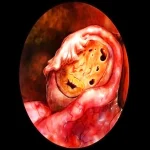

در سونوگرافی، جسم زرد (Corpora lutea) بهعنوان یک ساختار دایرهای یا بیضیشکل دیده میشود که پس از تخمکگذاری از فولیکول تخمدانی به وجود میآید. مشاهده جسم زرد در سونوگرافی معمولاً نشاندهنده این است که تخمکگذاری بهطور طبیعی انجام شده است و تخمک از فولیکول آزاد شده است. در واقع، جسم زرد بهعنوان یک ساختار موقتی در تخمدان باقی میماند که وظیفه تولید هورمونهای پروژسترون و استروژن را برای حفظ بارداری (در صورت وقوع) و حمایت از پوشش داخلی رحم دارد.

در سونوگرافی: مشاهده جسم زرد معمولاً بهعنوان یک ساختار کوچک، به اندازه ۱ تا ۲ سانتیمتر، در تخمدان ظاهر میشود. این ساختار ممکن است در قسمت تخمدان که در آن تخمکگذاری انجام شده، بهوضوح دیده شود.